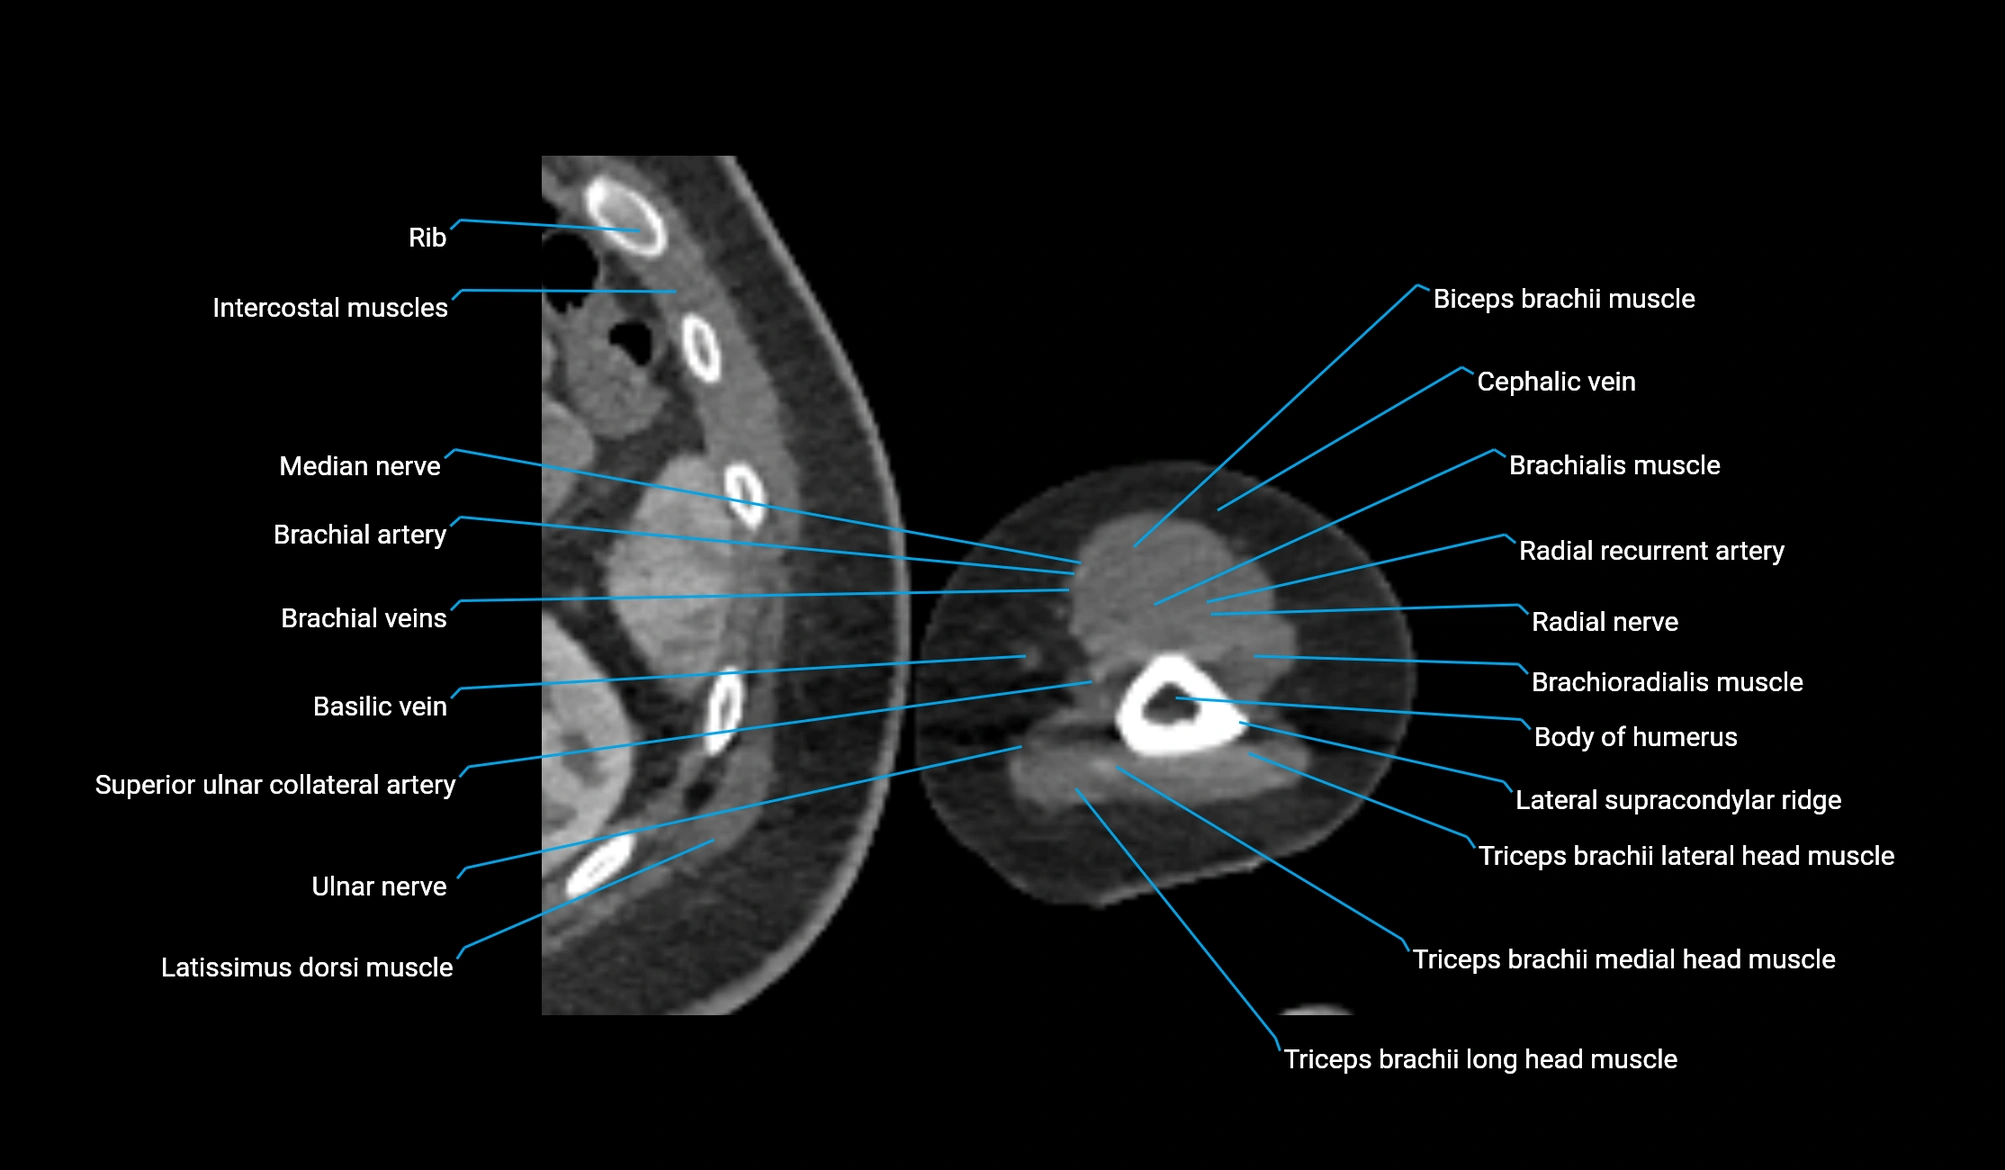

- Body of humerus

- Brachialis muscle

- Brachioradialis muscle

- Cephalic vein

- Deep brachial artery

- Lateral head of triceps brachii muscle

- Lateral supracondylar ridge

- Long head of triceps brachii muscle

- Medial head of triceps brachii muscle

- Median nerve

- Radial nerve

- Radial recurrent artery

- Superior ulnar collateral artery

- Triceps brachii muscle

- Ulnar nerve